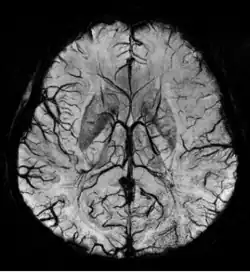

SWI venogram of a neonate with Sturge–Weber syndrome

An SWI venogram of a neonate with Sturge–Weber syndrome who did not display neurological symptoms is shown to the right. The initial conventional MR imaging methods did not demonstrate any abnormality. The abnormal venous vasculature in the left occipital lobe extending between the posterior horn of the ventricle and the cortical surface is clearly visible in the venogram. Due to the high resolution even collaterals can be resolved.